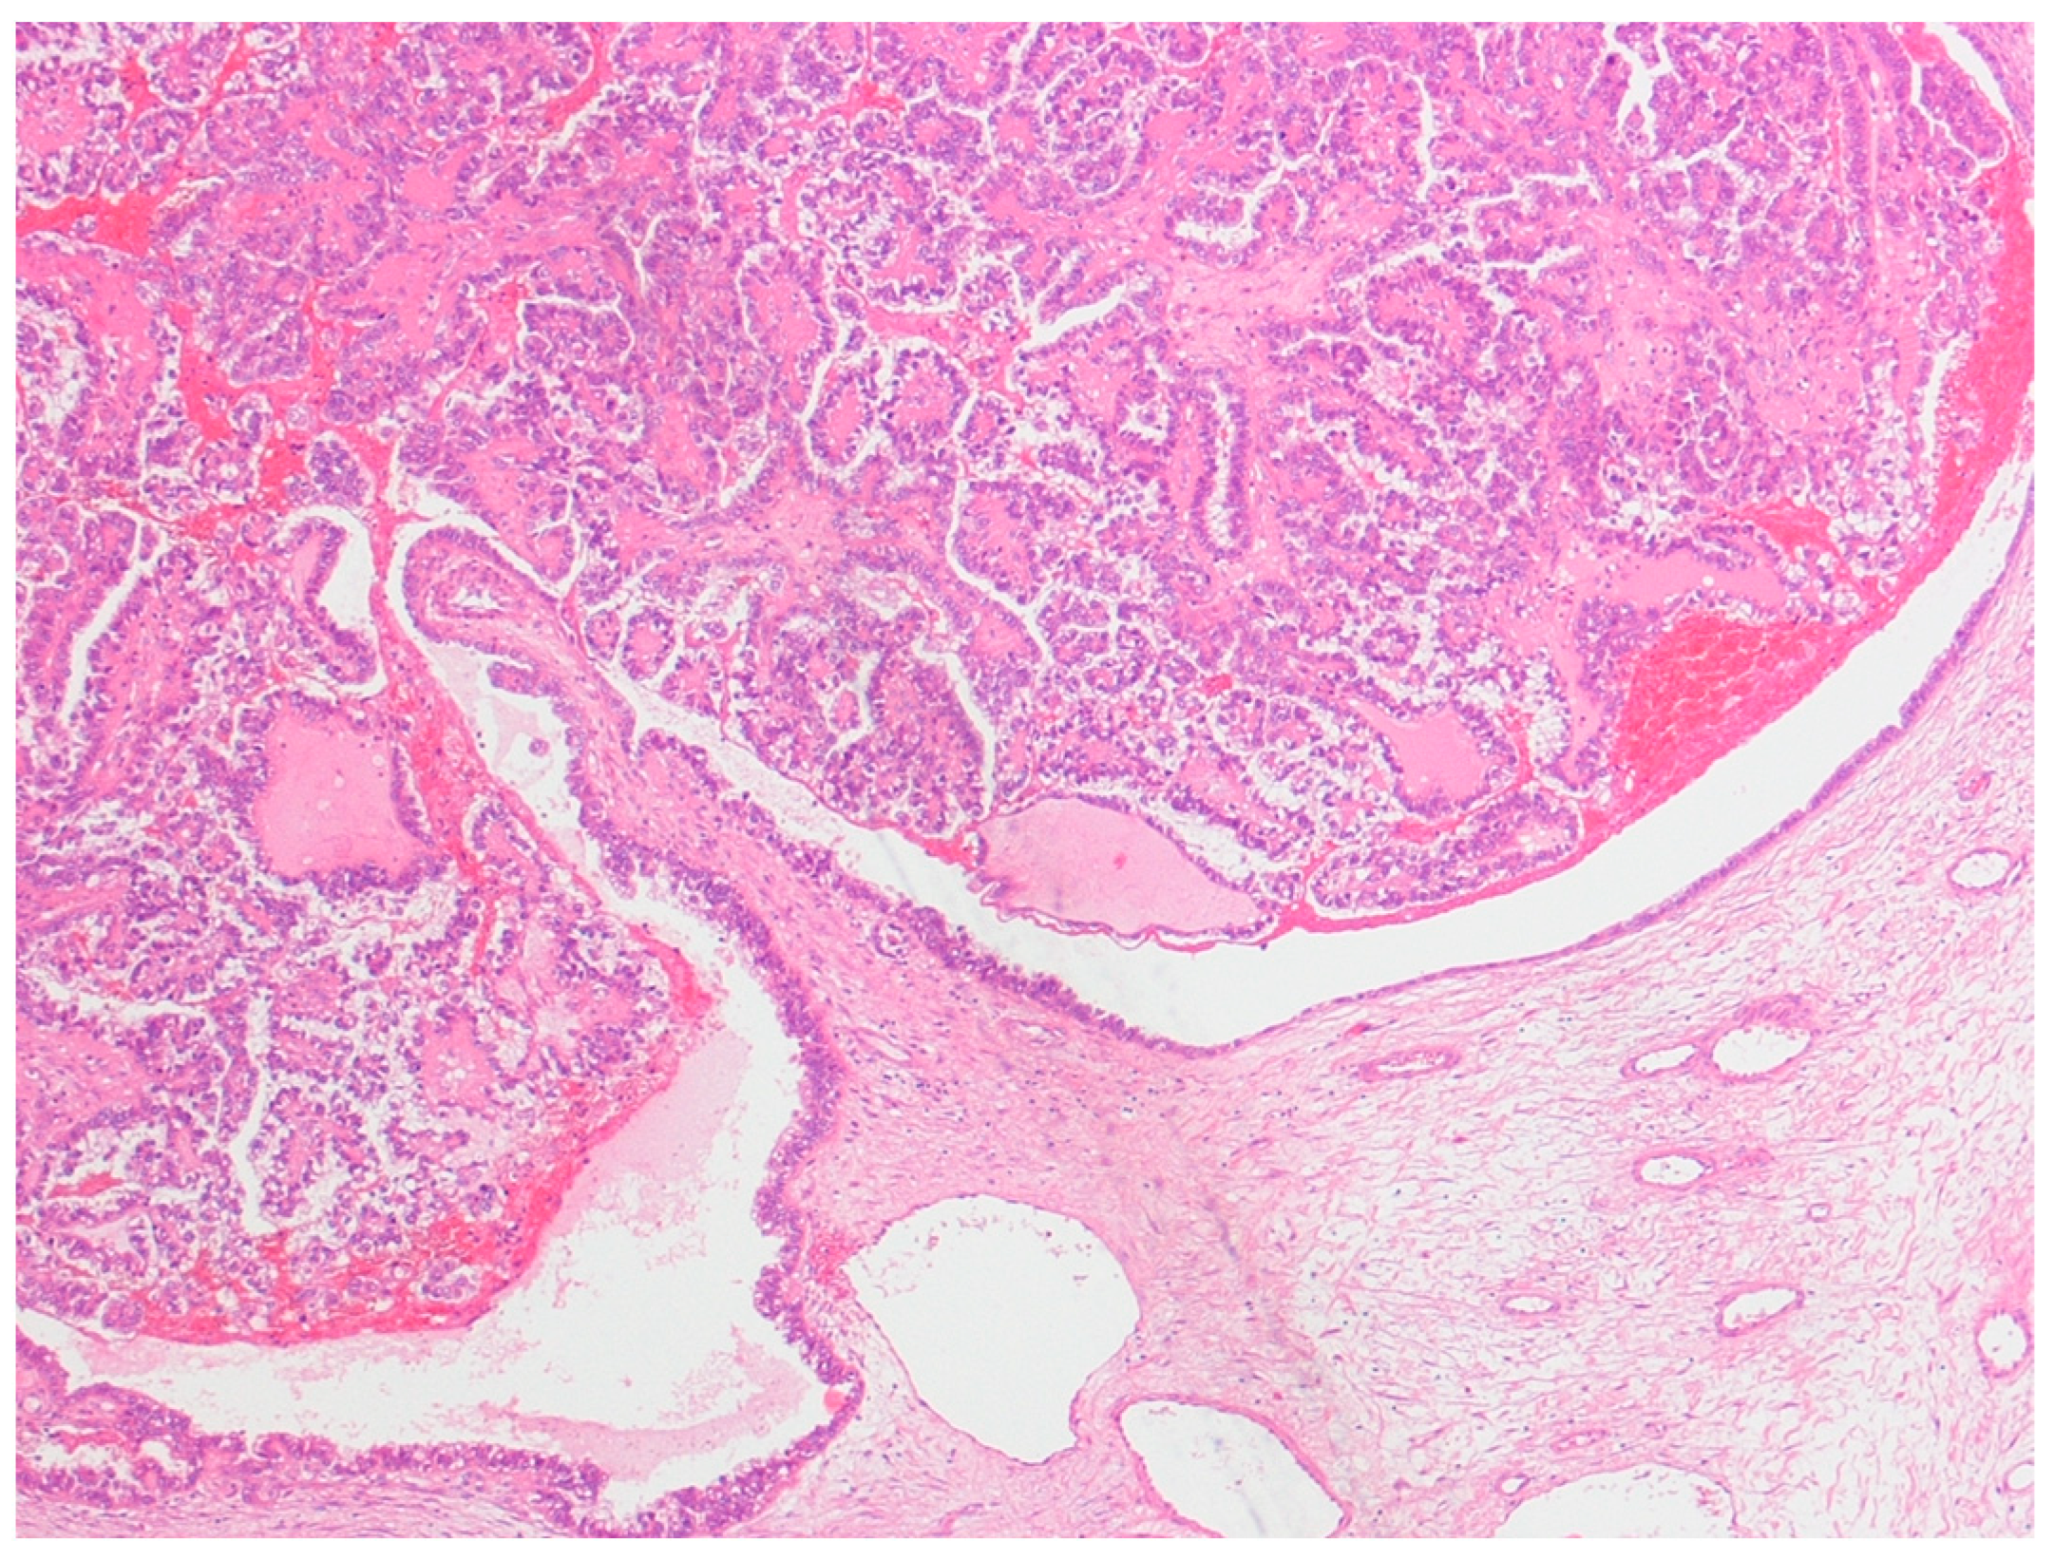

Figure 1. Clear cell carcinoma of the ovary arising in the lumen of an endometrioma, lined by columnar endometrioid cells. Hematoxylin and eosin × 150.

This was a retrospective study of 48 cases of ovarian tumors strictly associated with endometriosis, which were diagnosed and consecutively treated at the Obstetrics and Gynecology Unit of the Scientific Institute San Raffaele in Milan, Italy, between 1995 and 2016. Ethical approval was obtained from the San Raffaele Institute Ethics Board. All patients with a primary diagnosis of either pure clear cell ovarian cancer and mixed endometrioid–clear cell ovarian cancer strictly arising from endometriosis (ECC), or with endometriosis-associated endometrioid ovarian cancer (EAEOC), were included in the study. Patients whose diagnosis was made elsewhere were excluded. The definition of endometriosis arising from ovarian cancer was given according to Sampson’s [21] and Scott’s criteria [22], which included: (1) the coexistence of carcinoma and endometriosis in the same ovary; (2) the presence of tissue similar to endometrial stroma surrounding characteristic epithelial glands; (3) the exclusion of a metastatic tumor to the ovary and (4) the presence of benign endometriosis histologically contiguous with the malignant tissue. Patients with clear cell carcinoma associated with, but not arising from, endometriosis were excluded (Figure 1).